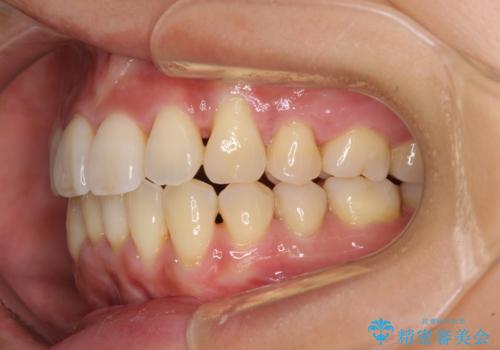

前歯のデコボコを治したい 費用を抑えた抜歯矯正

- 上下前歯のでこぼこを気にされ、矯正治療を希望された患者様です。

費用を抑えるため、メタルブラケットを採用し、抜歯矯正を行うこととしました。

通常であれば、上下顎左右小臼歯各1歯の合計4本を抜歯しますが、歯肉退縮の著しい下顎前歯を抜歯して欲しいという患者様の強い希望により、上顎のみ左右小臼歯2歯を、下顎は前歯を1歯を抜歯することとしました。

抜歯する歯を変更したため奥歯の咬合はアンバランスとなりましたが、前歯は綺麗に整い、歯肉退縮も回避できました。